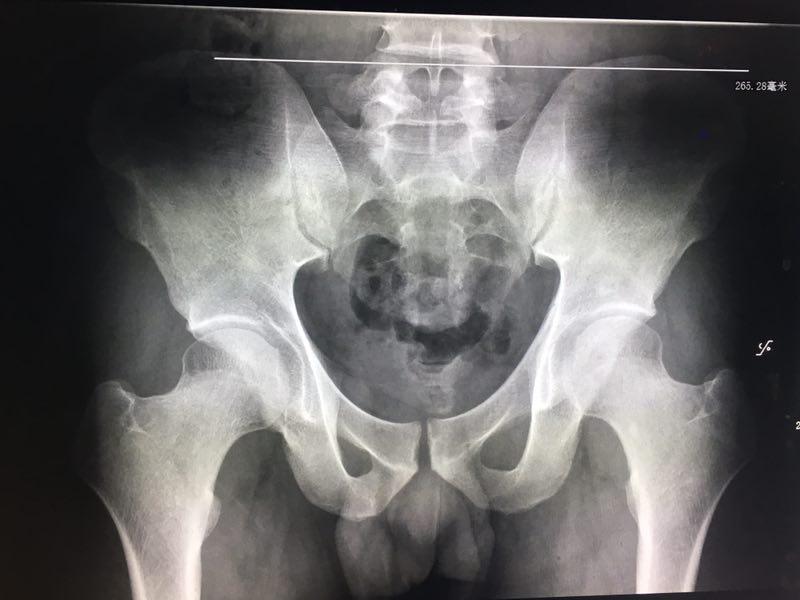

而如果是出现疼痛反复发作,但没有明显下肢麻涨无力或鞍区麻涨的表现,说明神经压迫不明显,也就是椎间盘突出的可能性不大,需要考虑是否有腰骶关节失稳或腰骶部软组织筋膜炎的问题,特别是骨盆失衡引起骶髂关节错位,造成骶髂关节炎症,进而诱发上半身代偿性劳损,导致腰骶部筋膜炎,就会出现疼痛反复发作的症状表现。另外也要考虑,有的患者是存在先天性的骨发育不良的问题,像腰椎骶化 横突过长 髋臼发育不良等问题,都有可能诱发骶髂关节间隙变窄,引起骶髂关节炎症导致疼痛不适。

这类情况可以去中医院的骨伤科或理疗科就诊,进行体征检查及触诊,必要时可以拍摄站立位的骨盆平片观察,才能鉴别诊断。通常像局部筋膜炎的问题,可以口服非甾体类药物及局部药敷缓解炎症刺激,还可以配合针灸 红外 超声波松解这类治疗,而如果有骶髂关节错位 腰骶关节失稳的问题,可以通过手法调整关节,减轻关节压力,从而改善症状,而且在后期主要还是自己配合功能锻炼恢复,通过功能锻炼增强核心肌肉力量,保持关节稳定,才能预防恶化及复发。